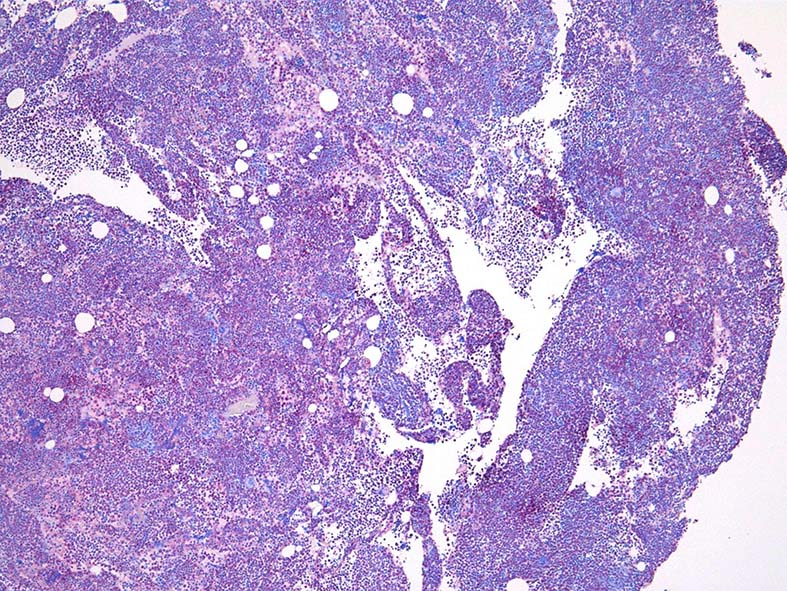

骨髄組織所見 (thumbnailのクリックで大きな画像がみられます)

Fig.01: hypercellular marrow. ASDで赤染する細胞の増加=granulopoietic hyperplasiaがある.

Fig.03: granulopoietic hyperplasia. 成熟顆粒球の増加もある.